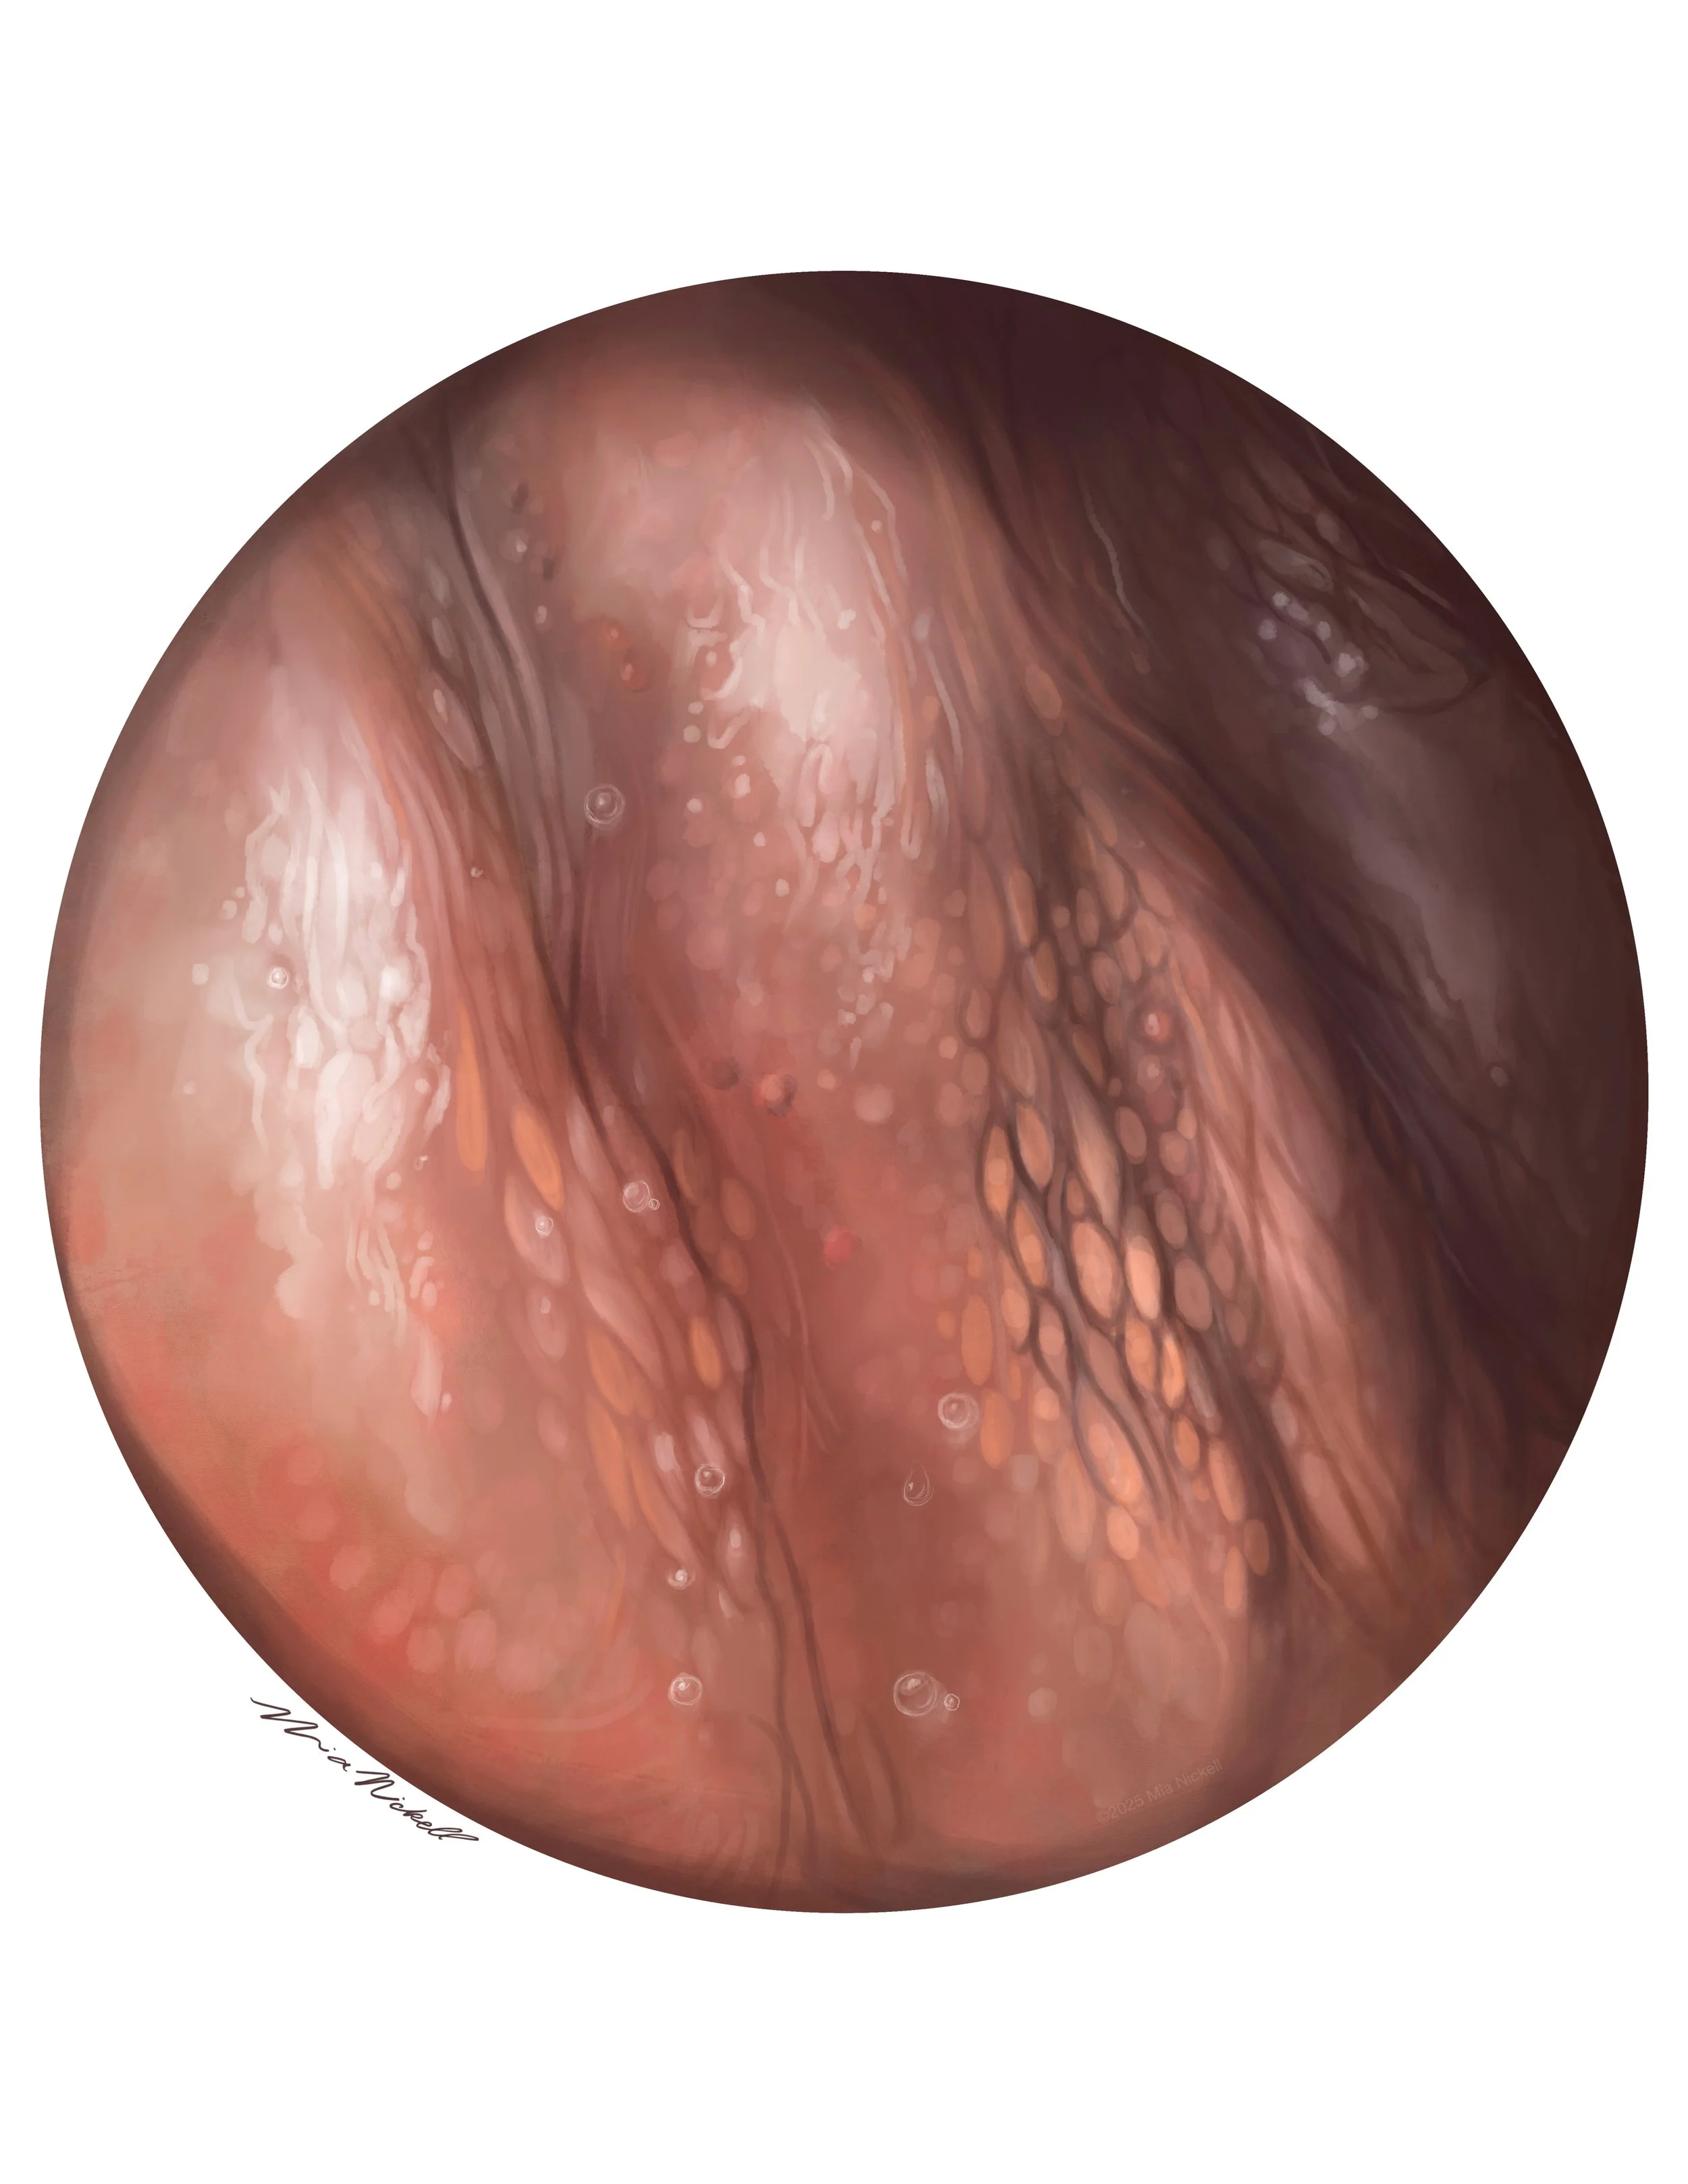

The Heart, Still Life | Graphite, Adobe Photoshop